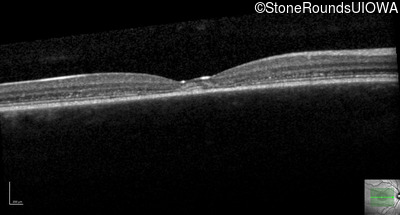

Optical Coherence Tomography - Left - 20/20 -2

Exemplar / OCT Stack